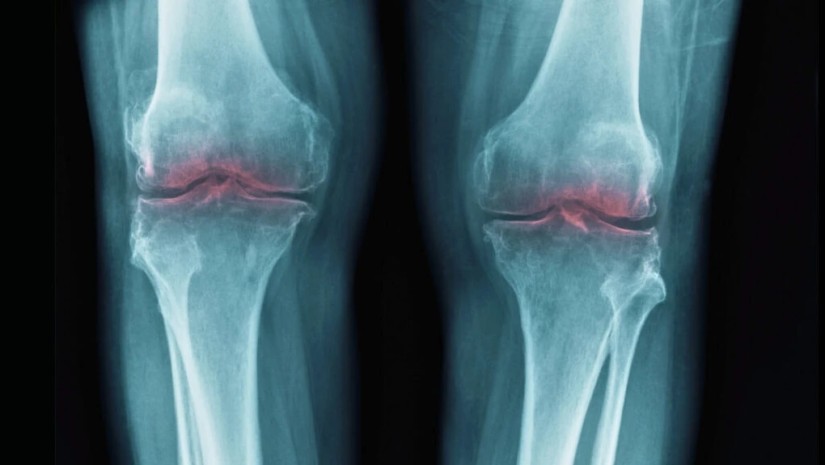

კარგი ამბავი და დიდი გარღვევა ოსტეოართრიტის მკურნალობაში - მეცნიერებმა ასაკით დაზიანებული სახსრების ხრტილები აღადგინეს

მეცნიერებმა ასაკით დაზიანებული სახსრების ხრტილები აღადგინეს

ამან მეცნიერები აიძულა განეხილათ, შესაძლოა თუ არა 15-PGDH ჩართული იყოს ოსტეოართრიტში — დაავადებაში, რომელშიც სახსრებზე დატვირთვა განაპირობებს ხრტილში კოლაგენის დაშლას, რაც ანთებას და ტკივილს იწვევს.